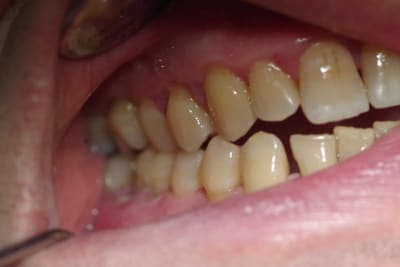

Le patient de 65 ans n'a plus d'occlusion sur le secteur ant et sur le secteur postérieur gauche.

L'occlusion ne se fait que sur les 5, 6 et 7 côté droit.

De ce fait la surcharge occlusale sur la 46 a entraîné une lyse osseuse importante qui contre indique la conservation de cette dent.

J'ai d'abord pensé adresser le patient pour une rééducation linguale ( kiné ou orthophoniste) car le patient a une langue très puissante qui a entraîné l'inocclusion totale des secteurs antérieurs et latéraux ( côté gauche).

A priori le patient m'a juste rapporté un épisode de blocage il y a 2-3 mois mais cela n'a duré que qq secondes. A la palpation je ne sens pas de vacuité au niveau de la cavité glénoîde. L'ouverture me semble légèrement asymétrique mais il n'y a aucun craquement ni douleur à ce moment là.

Je pencherai plutôt vers une déformation de son maxillaire due à une pulsion linguale importante.